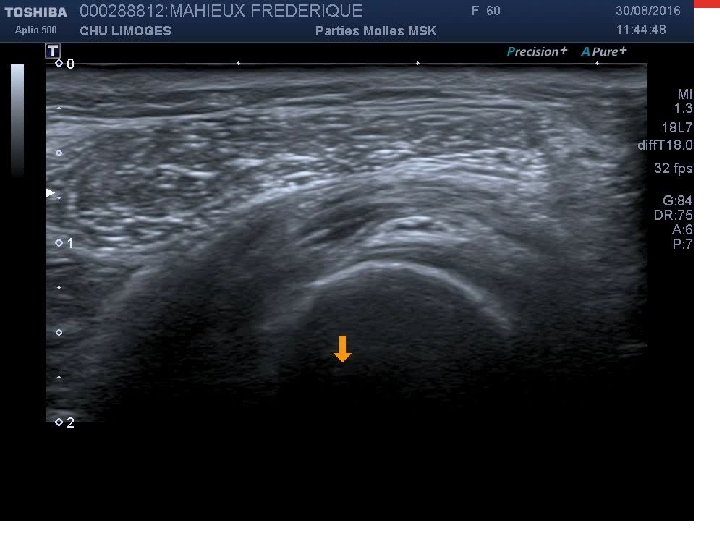

Cas clinique 4 • Footballeur de 28 ans, entorse de cheville à répétition, consulte pour des douleurs profondes postérieures associées à une instabilité. • A l’examen, douleur postérieure sans atteinte du tendon calcanéen. Laxité sagitale. • Radio: Pas de fracture Suspicion d’un syndrome du carrefour postérieur

Cas clinique 4 (suite): Buts de l’écho • Poser le diagnostic • Recher des facteurs de gravité • Guider le traitement

Infiltration du carrefour postérieur

Infiltration carrefour postérieur LFH

Infiltration carrefour postérieur